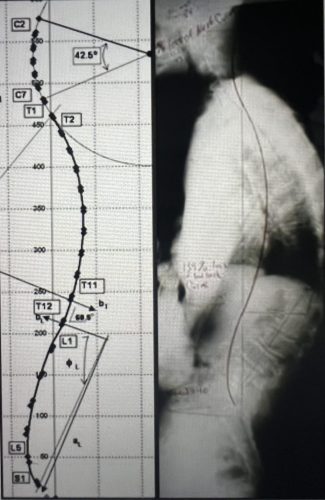

Increase Disc Height in 64 Cases - First Evidence of Aging Reversal in Published Study